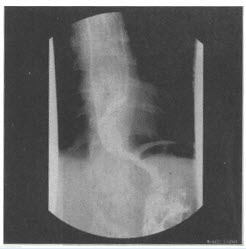

患者,男,25岁。近几年出现吞咽梗阻感,偶出现胸骨后疼痛。行食管吞钡检查如图。

对该病的描述

不正确

的是()

A:病因是食管神经肌肉运动功能障碍,下段食管括约肌呈失弛缓状态而导致食管张力减退、蠕动消失及食管扩张

B:临床上以吞咽困难、胸骨后疼痛及食物反流为最常见的症状

C:最常见于老年人

D:是一种非器质性食管狭窄性疾病

E:典型的X线表现为食管狭窄并其上段极度扩张

F:以上都不是